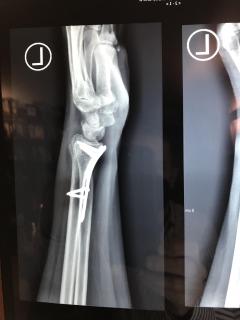

Περίπτωση 2ου ασθενούς